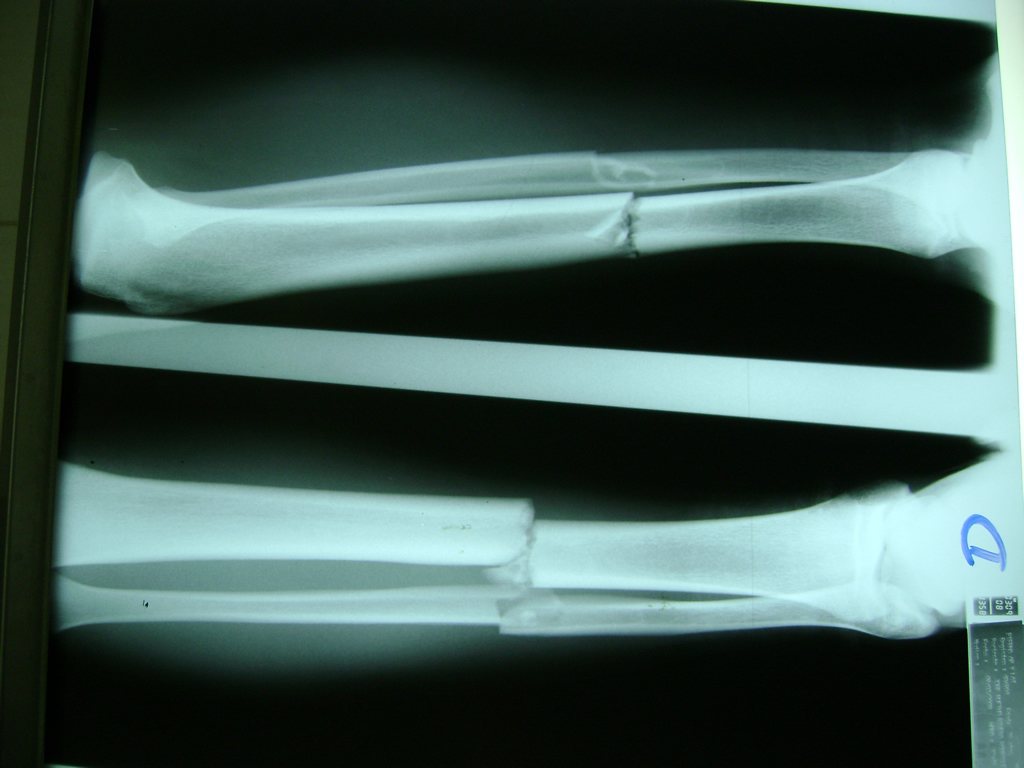

Cirugias en El Salvador - Perone y Tibia

Aunque cada uno de estos huesos puede fracturarse por separado, normalmente la rotura es una lesión que se produce de forma conjunta

La mayor parte de las roturas implican a la parte proximal del hueso (parte del hueso próximo a la rodilla) o a la parte distal (parte del hueso cerca del tobillo).

Debido a la fina cobertura de piel que recubre la tibia y el peroné, las fracturas generalmente son abiertas, es decir, el hueso roto rasga la piel, atravesándola. Las fracturas de tibia y peroné generalmente se producen por un fuerte impacto o torsión.